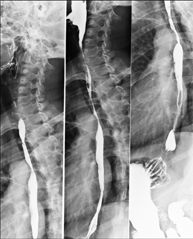

Tècnica que usa els raigs X a través de la qual s'obtenen imatges de la columna dorsal per al seu estudi. Indicacions: traumatisme, dolor, escoliosi. - Esofagograma

Prova diagnòstica que consisteix en obtenir imatges radiològiques en moviment de l'esòfag mitjançant l'ús de raigs X (fluorosòpia) i d'un contrast opac baritat que s'administra per via oral.

Tècnica que usa els raigs X a través de la qual s'obtenen imatges de la columna lumbar per al seu estudi. - TEGD (trànsit esòfag-gastro-duodenal)

Prova diagnòstica que consisteix en obtenir imatges radiològiques en moviment de l'esòfag, estómac i duodè mitjançant l'ús de raigs X (fluoroscòpia) i d'un contrast opac baritat que s'administra per via oral. - Trànsit intestinal

Prova diagnòstica que consisteix en obtenir imatges radiològiques en moviment de l'esòfag, estómac, duodè i intestí prim mitjançant l'ús de raigs X (fluoroscòpia) i d'un contrast opac baritat que s'administra per via oral. - Ènema opac doble contrast

Tècnica que usa els raigs X a través de la qual s'obtenen imatges de la columna dorsal per al seu estudi. Indicacions: traumatisme, mal d'esquena. - RX Columna lumbar

Tècnica que usa els raigs X a través de la qual s'obtenen imatges de la columna lumbar per al seu estudi. Indicacions: ciàtica, traumatisme, dolor lumbar. - RX Sacre-còccix

Tècnica que usa els raigs X a través de la qual s'obtenen imatges del sacre i del còccix per al seu estudi. Indicacions: traumatisme, dolor sacre o coccigi. - Telerradiologia columna

Tècnica que usa els raigs X a través de la qual s'obtenen imatges de tota la columna vertebral per al seu estudi, amb la valoració especialment de la presència d'escoliosi i dismetries pèlviques.